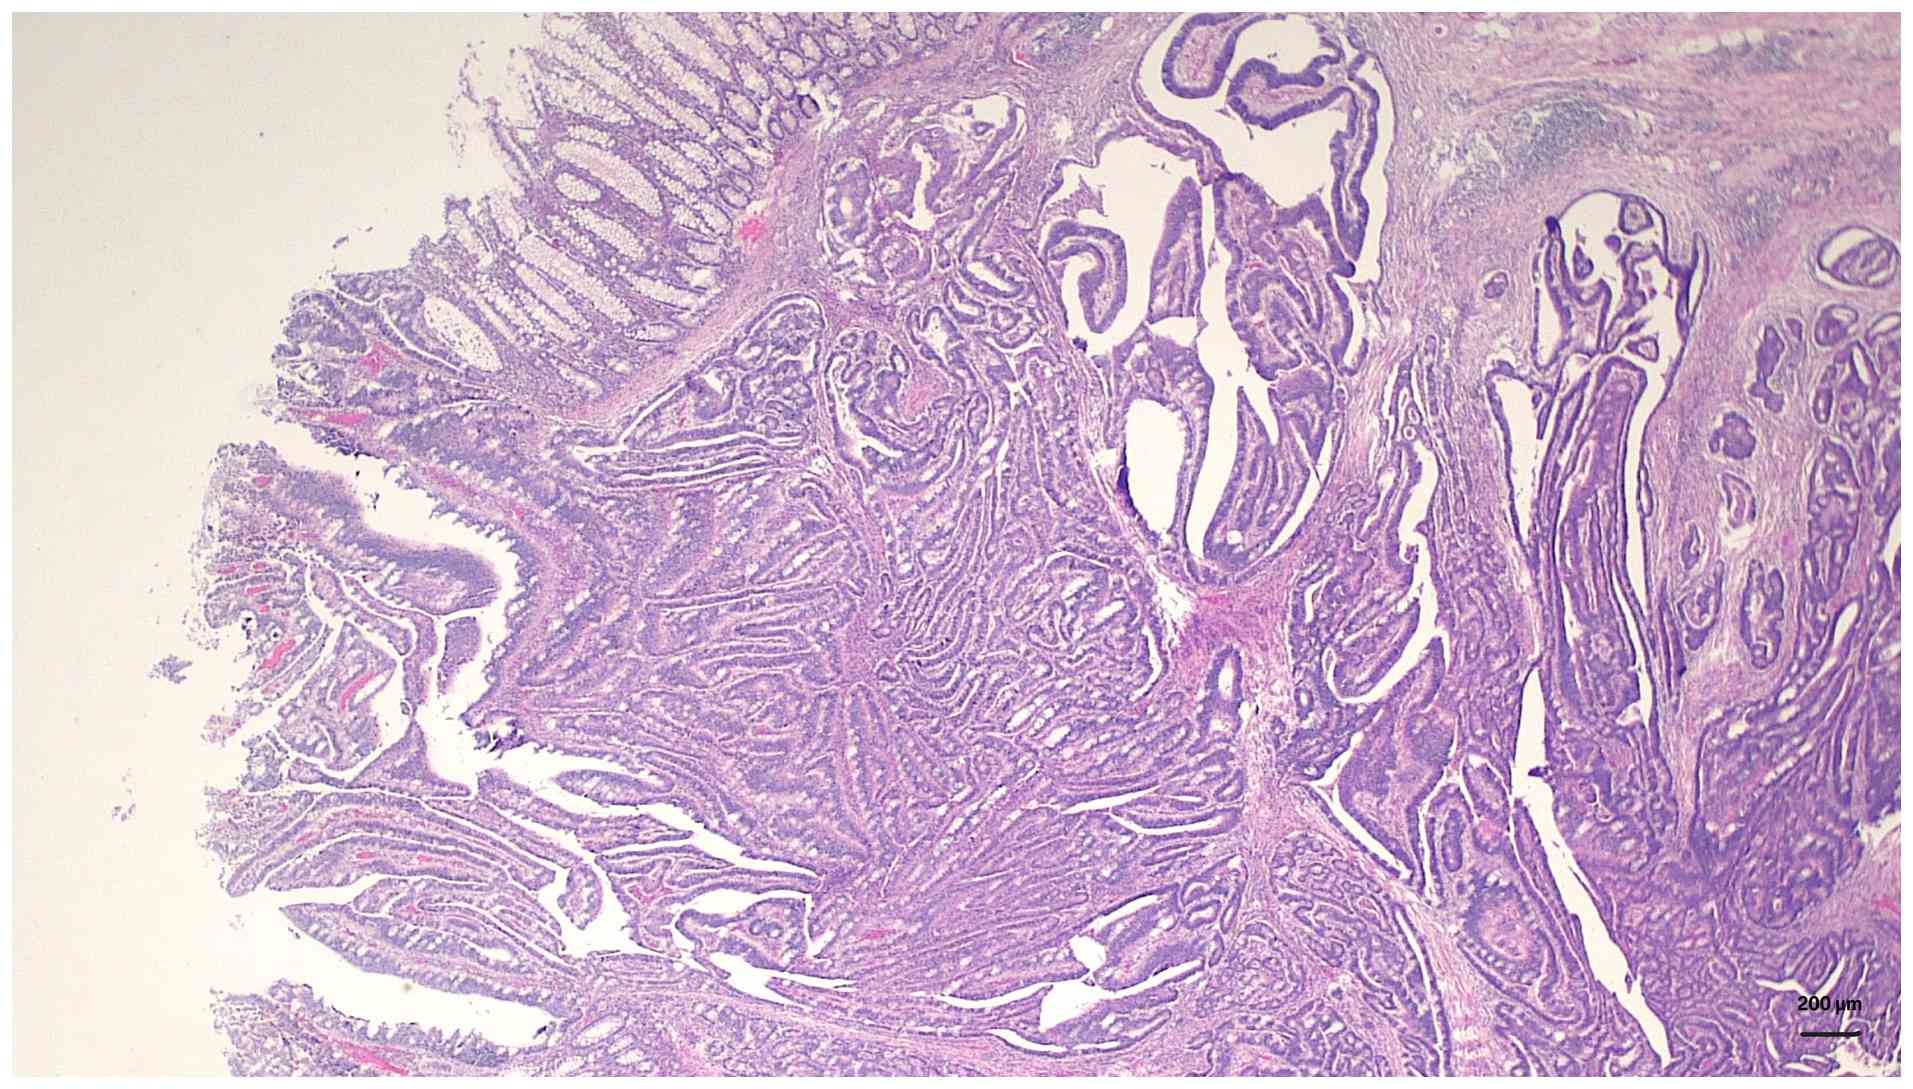

Given the extensive colonic polyposis and confirmed malignancy at the hepatic flexure, the patient underwent a subtotal colectomy with end-to-end ileorectal anastomosis. Postoperative histopathological analysis confirmed a moderately differentiated adenocarcinoma of the hepatic flexure, which was staged as pT3N0M0 (Stage IIA), along with >100 tubulovillous adenomas observed throughout the resected colon (Fig. 2B). Paraffin-embedded tissue sections were stained with hematoxylin and eosin (H&E) according to a standard protocol. Briefly, tissue samples were fixed in 10% neutral buffered formalin at room temperature (~22˚C) for 8 h before being embedded in paraffin. Sections 4-µm thick were cut using a microtome. H&E staining was performed with hematoxylin at room temperature for 10 min followed by eosin for 2 min. Histopathological examination revealed irregular dysplastic glands infiltrating into the submucosa and muscularis propria, accompanied by a prominent desmoplastic stromal reaction (Fig. 3). At higher magnification, the tumor was found to have an atypical glandular structure with nuclear pleomorphism, hyperchromasia and loss of normal glandular polarity within a fibrotic stroma, consistent with moderately differentiated adenocarcinoma (Fig. 4).

Histopathological examination at low

magnification, revealing irregular dysplastic glands infiltrating

into the submucosa and muscularis propria, accompanied by a

prominent desmoplastic stromal reaction (hematoxylin and eosin;

magnification, x100; scale bar, 200 µm).

Figure 3

Histopathological examination at low magnification, revealing irregular dysplastic glands infiltrating into the submucosa and muscularis propria, accompanied by a prominent desmoplastic stromal reaction (hematoxylin and eosin; magnification, x100; scale bar, 200 µm).